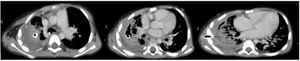

A los 24 días de su ingreso en UCI se realizó una TC de tórax (fig. 1) en la que se observó una neumonía necrotizante con signos de una probable fístula broncopleural. El paciente fue mejorando progresivamente, lo que permitió la realización de una traqueostomía al mes de ingreso y la desconexión de la ventilación invasiva en el día 45, sin embargo, el paciente mantenía la fuga aérea a través del tubo de drenaje torácico.